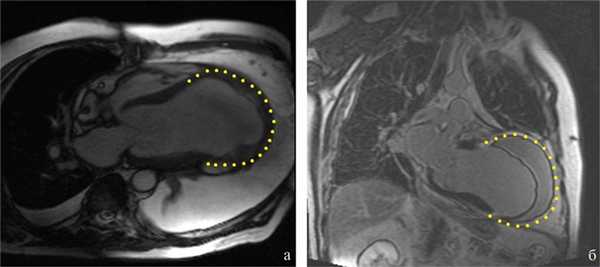

МРТ сердца: обширные рубцовые изменения миокарда ЛЖ переднеперегородочной, боковой и верхушечной локализаций с наличием массивного пристеночного тромбоза в области рубца. Площадь рубцовой трансформации миокарда составила 85% площади ЛЖ. КДО ЛЖ до 750 мл, КДР ЛЖ 11,5 мм, КСР ЛЖ 11,2 мм. Критическое снижение сократимости миокарда ЛЖ (рис. 1).

Рис. 1. МРТ сердца до операции. а — четырехкамерная проекция; б — двухкамерная проекция. Желтая пунктирная линия — границы рубцовой ткани.